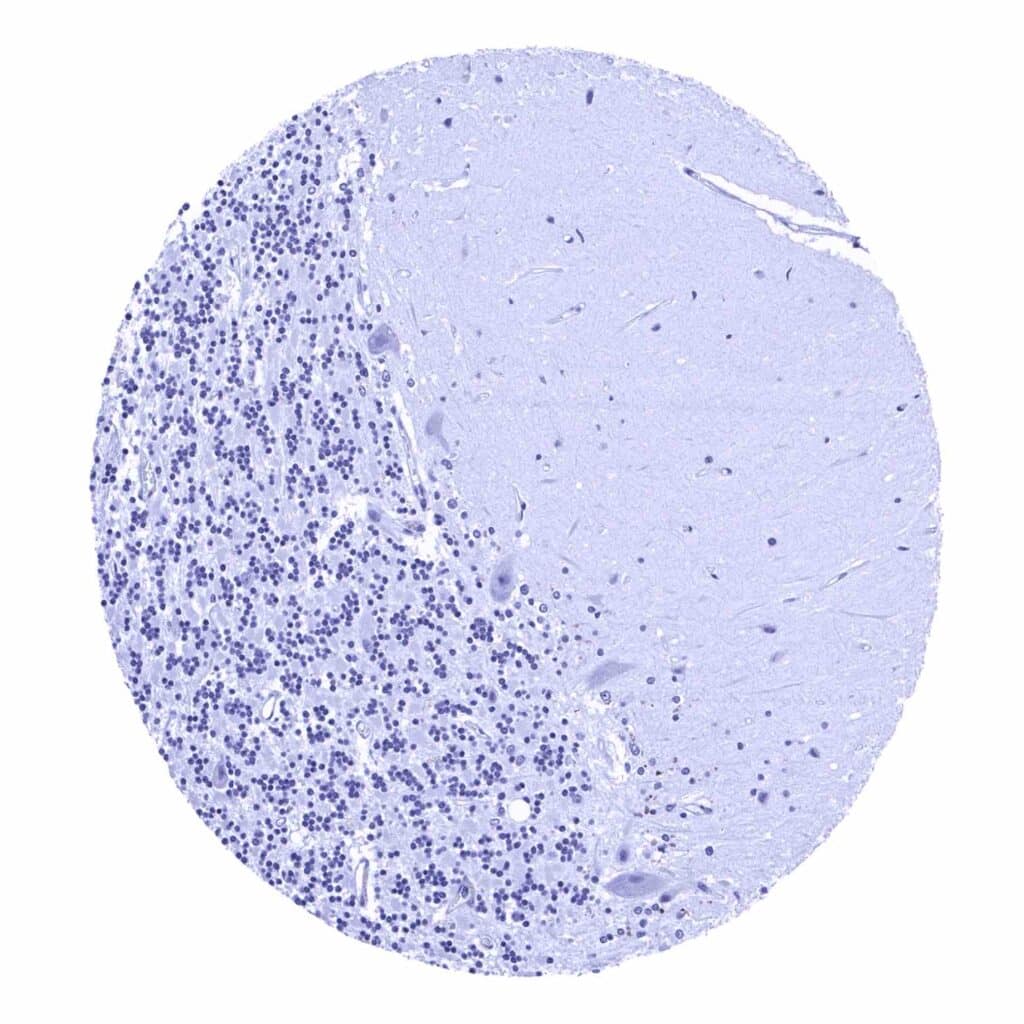

Cerebellum (molecular layer, Purkinje cell layer, granule cell layer, white matter)